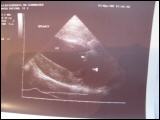

Die Ultraschalluntersuchung ist ein bildgebendes Verfahren zur Darstellung verschiedener Organerkrankungen. Dabei stehen Erkrankungen der Weichteilorgane im Vordergrund. Wir verfügen in unserer Praxis ein Ultraschallgerät mit Farb- und konventionellem Doppler und können eine Vielzahl von Ultraschalluntersuchungen durchführen.

Herzerkrankungen - Dopplerchokardiographie -

Herzuntersuchung beim Hund